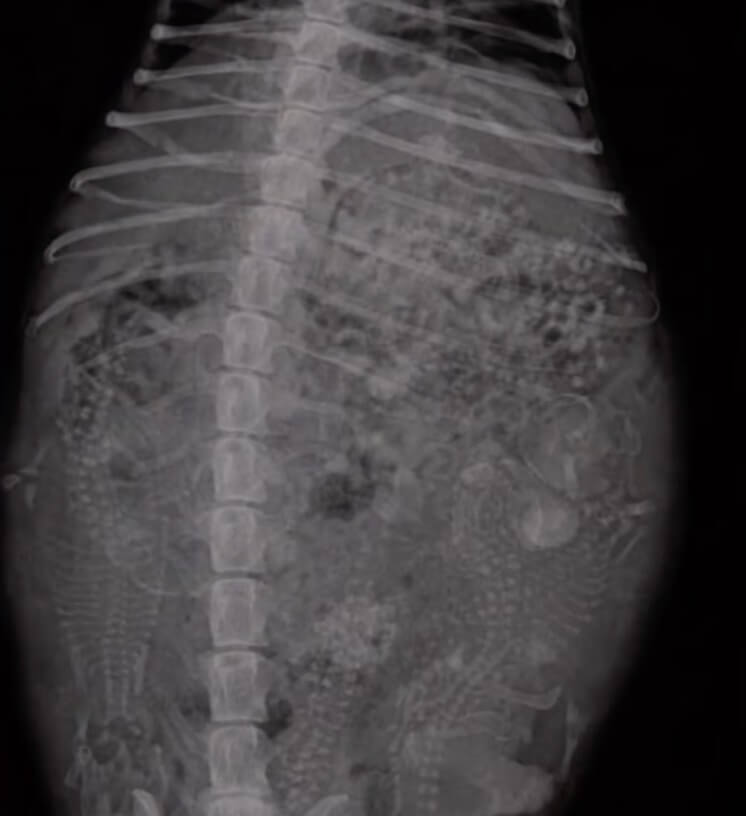

The only way to know for sure was an ultrasound.

When the scan appeared on the screen, the room grew quiet.

The dog was not suffering from fluid buildup.

She was pregnant.

Very pregnant.

Five tiny puppies were growing inside her.